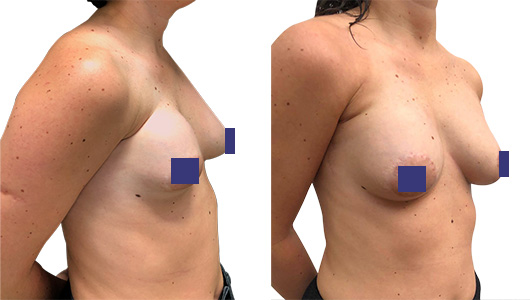

Vorne wird eine neuer, größerer Hohlraum für das neue weiche, mit Silikongel gefüllte Brustimplantat geschaffen. Remodellierung der tuberösen und ptosierten linken Brust mit periareolärer Dermo-Mastopexie.

Symmetrische Repositionierung des Warzenhofs der rechten Brust.

Das unmittelbare Ergebnis ist für den Patienten sehr zufriedenstellend (Abb.3). Die Thorax- und Brustsymmetrie ist stark verbessert.